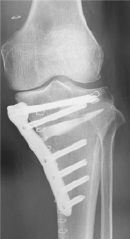

高位脛骨骨切り術OWHTO

人工膝関節

単顆置換術UKA

置換術(MA法)MA TKA

置換術(KA法)KA TKA